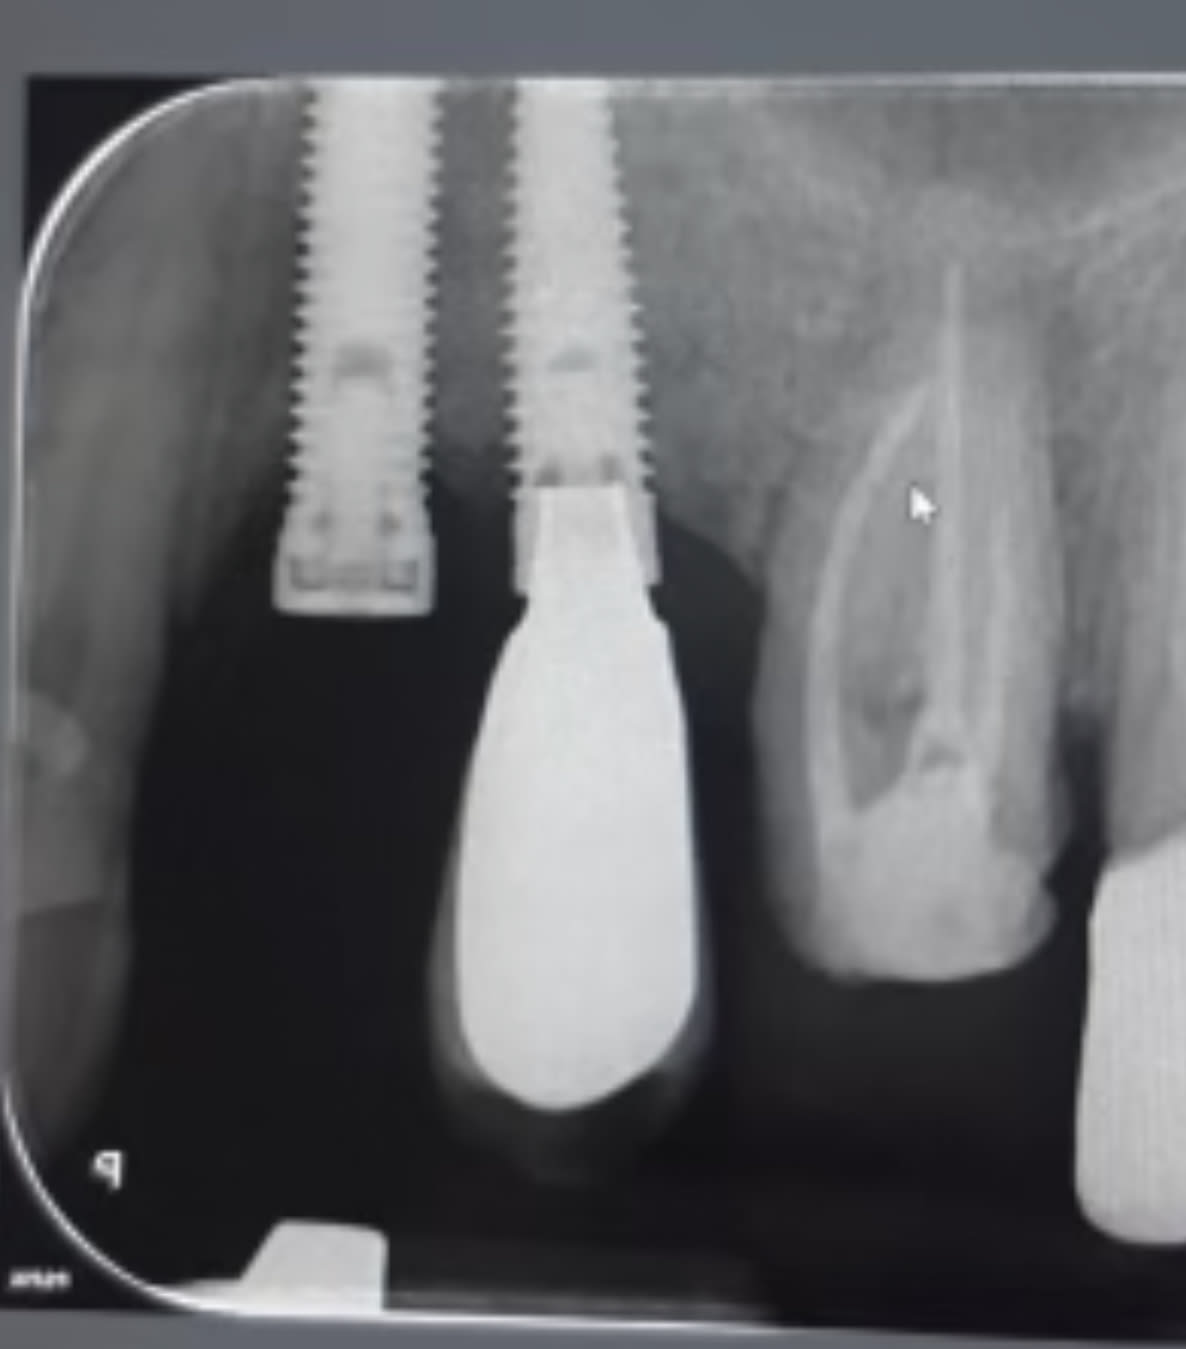

pourrais-tu me dire la marque de ces implants

Kontact de chez Biotech ….!